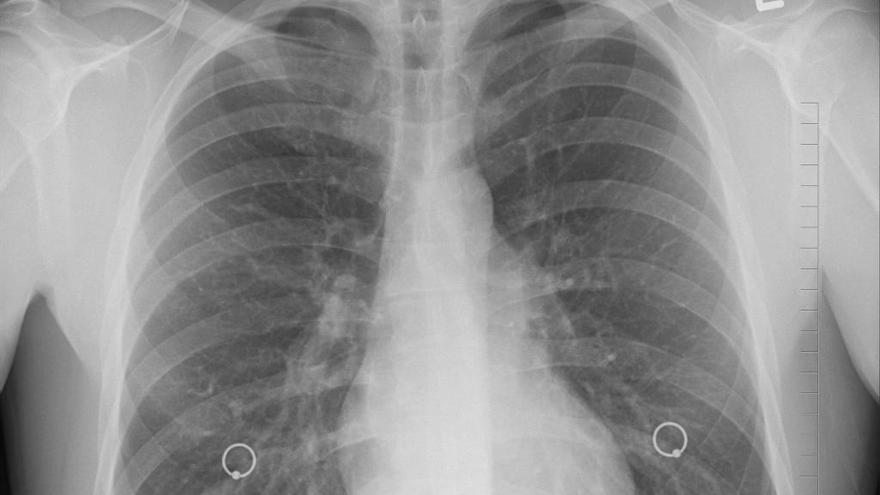

El cáncer de pulmón es la principal causa de muerte por cáncer en todo el mundo. Cada año se diagnostica la enfermedad a más de 2 millones de personas en todo el planeta. La mayoría de quienes desarrollan un cáncer de pulmón tienen un historial de tabaquismo, pero entre el 10% y el 20% nunca han fumado y ese cáncer de pulmón en los que nunca han fumado se da con más frecuencia en las mujeres y a una edad más temprana que el cáncer de pulmón en los fumadores.

En este amplio estudio epidemiológico, los investigadores utilizaron la secuenciación del genoma completo para caracterizar los cambios genómicos en el tejido tumoral y en el tejido normal correspondiente de 232 no fumadores, predominantemente de ascendencia europea, a los que se les había diagnosticado cáncer de pulmón de células no pequeñas. Los tumores incluían 189 adenocarcinomas (el tipo más común de cáncer de pulmón), 36 carcinoides y otros siete tumores de diversos tipos. Los pacientes aún no habían recibido tratamiento para su cáncer.